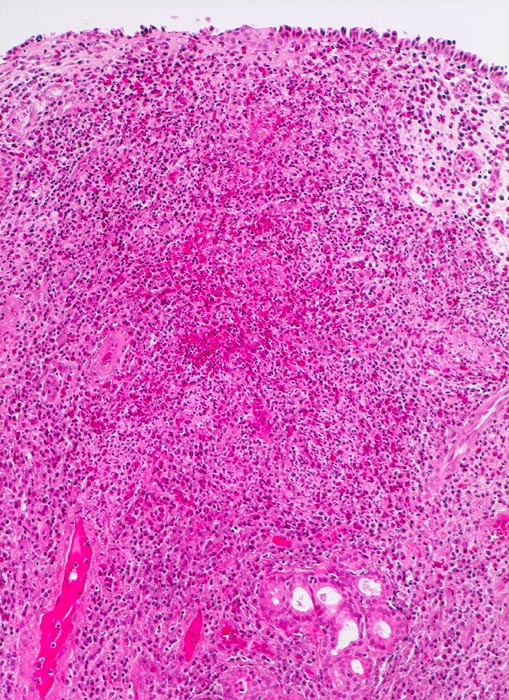

chronische polypöse Rhinitis

Einzelne seromuköse Schleimdrüsen und sehr dichtes gemischtes Entzündungsinfiltrat im vermehrten Stroma.

Patient mit nicht allergischem Asthma klagt über chronische dumpfe Kopfschmerzen und behinderte Nasenatmung. Bei der anterioren Rhinoskopie sind multiple Polypen der Nasenschleimhaut im Bereich des mittleren Meatus sichtbar.

Histologie

100